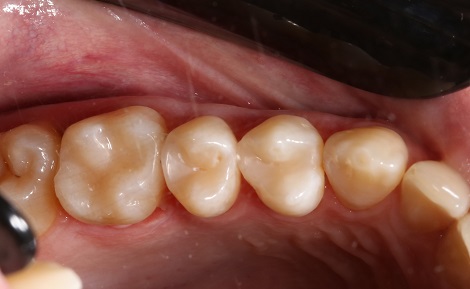

Якісно запломбовані кореневі канали є основою довговічності. Тому очищення і пломбування кореневих каналів в «Домі Стоматології» приділяється особлива увага! Після пломбування кореневих каналів проводиться контроль якості пломбування за допомогою знімка.

2. Забезпечення щільного прилягання пломби до емалі після лікування зуба — ідеальна поверхня, відсутність мікротріщин і нерівностей — гарантія надійності і довговічності пломби.